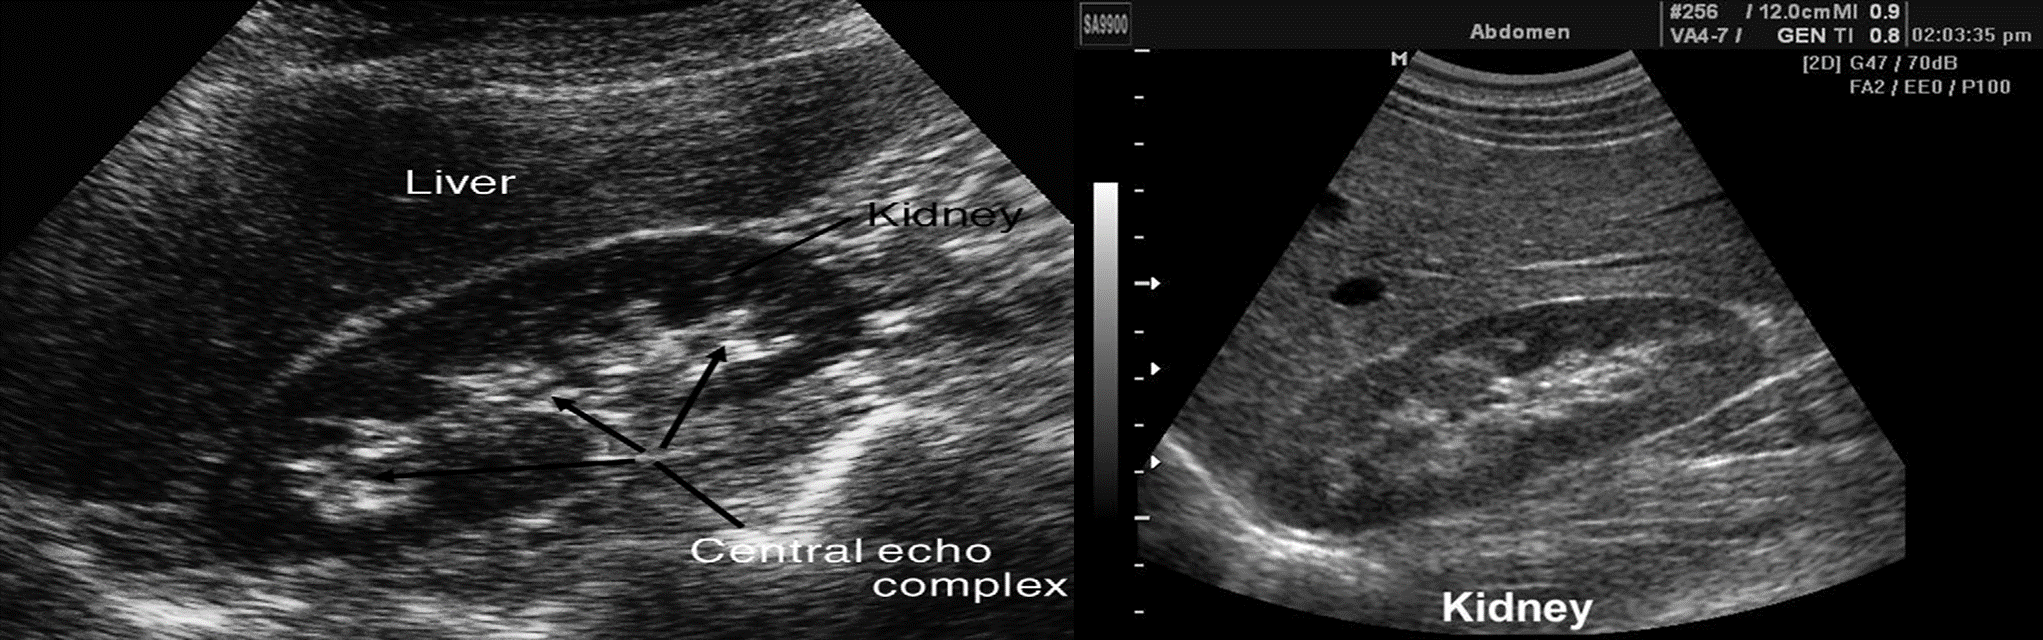

The kidneys should be smooth in outline. The parenchyma surrounds a central echogenic region, known as the central echo complex (the renal sinus), consisting of the pelvicaliceal system, together with the surrounding fat and renal blood vessels.

The renal cortex generates homogeneous echoes that are of equal or less reflective than those of the adjacent liver or spleen.

The renal pyramids are seen as triangular hypoechoic areas adjacent to the renal sinus.